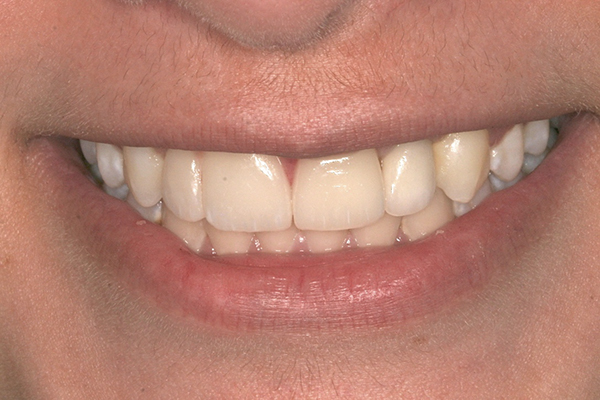

Fig 1 and Fig 2. Pretreatment photographs. Patient at 9 years of age on presentation.

A 9-year-old girl, referred to a prosthodontic office by her pediatric dentist, presented with her mother’s chief complaint: “The kids are teasing her about her big front tooth.” Findings from radiographic and clinical examinations revealed fused maxillary central-peg lateral incisors, teeth Nos. 7 and 8, and a congenitally missing lateral incisor, tooth No. 10 (Figure 1 through Figure 3). An implant was selected as the ideal treatment to replace tooth No. 10 when somatic growth was complete. A diagnostic wax-up was fabricated to determine if the fused tooth could be made to resemble two teeth, using pink composite to give the illusion of an interproximal papilla. The patient was referred for an orthodontic consultation to plan for closure of the diastema between teeth Nos. 8 and 9 and achievement of proper alignment for implant No. 10. The patient was also referred to a periodontist for pretreatment assessment of the tooth No. 10 site. An endodontist was consulted should exposure of the large pulp occur during tooth preparation.

When the patient was 19 years old, the lithium-disilicate veneers and the ceramic crown were tried in and evaluated. Following modification, the veneers were carefully cemented with an adhesive resin cement following application of silane to the intaglio surfaces, etch of the enamel, and application of primer and adhesive. The intaglio surface of the implant crown was treated with a porcelain etch product and silane, and the crown was cemented with carboxylate luting cement with 1 drop of water for retrievability. A paintbrush was used to apply a thin layer of cement to minimize excess. Any excess cement on the veneers and crown was meticulously removed, and the margins and occlusion were carefully checked. The patient returned 2 weeks later (Figure 13 through Figure 18) for a review of her oral hygiene and for fabrication of a nightguard. The patient was happy with the esthetic result and exclaimed she had been stopped on the street and told she had a beautiful smile.